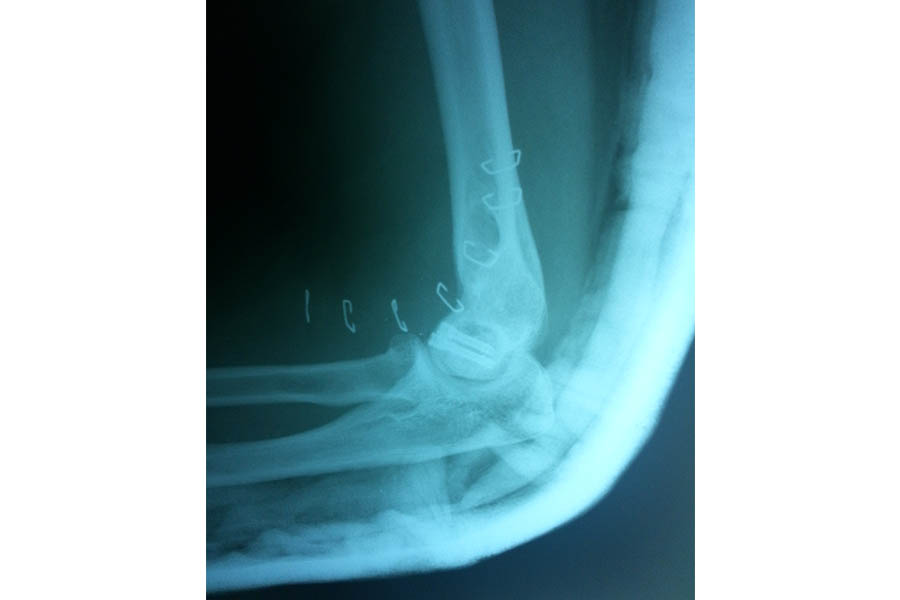

Total Elbow Replacement

Case 1